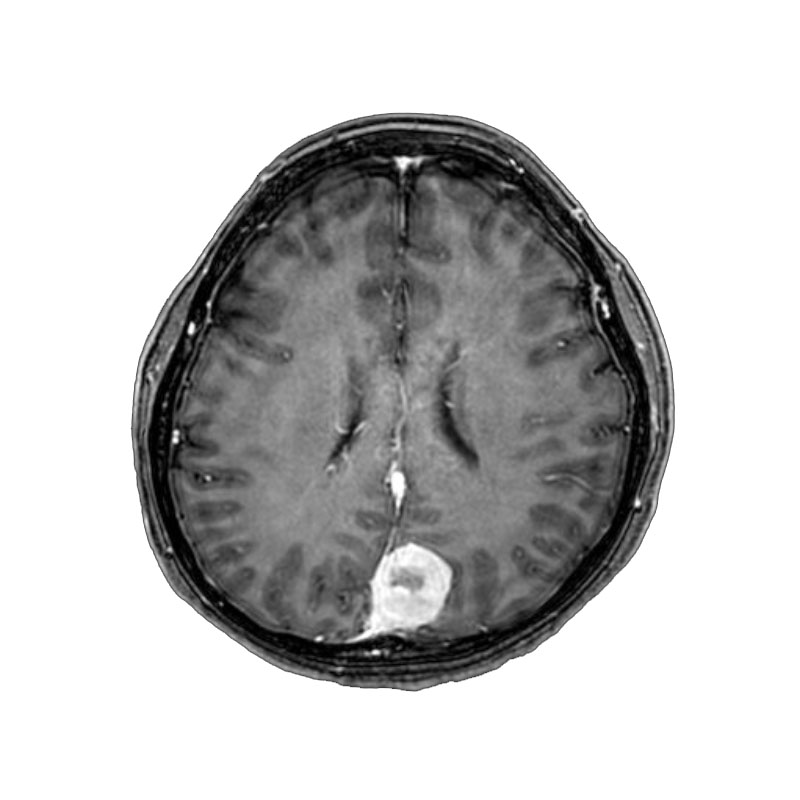

脳室内腫瘍

摘出術

北野/濵田